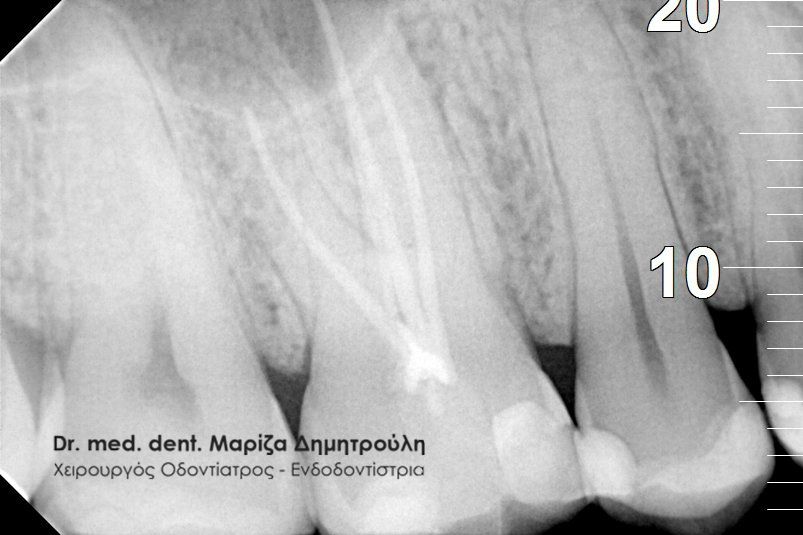

Στο συγκεκριμένο περιστατικό είχε πραγματοποιηθεί από συνάδελφο απονεύρωση δοντιού και ο ασθενής αναφέρει τις έντονες ενοχλήσεις που του προκαλεί το δόντι το τελευταίο τρίμηνο. Η ακτινογραφία αποκάλυψε αφενός το μικρό μήκος της απονεύρωσης στην εγγύς ρίζα του δοντιού και αφετέρου την ύπαρξη περιακρορριζικής αλλοίωσης στην άπω ρίζα δοντιού, η οποία έχει τη μορφή μιας μαύρης σαφώς περιγεγραμμένης σκιάς. Η εμφάνιση της αλλοίωσης αυτής σημαίνει οτι το δόντι έχει φλεγμονή, η οποία πρέπει να αντιμετωπιστεί.